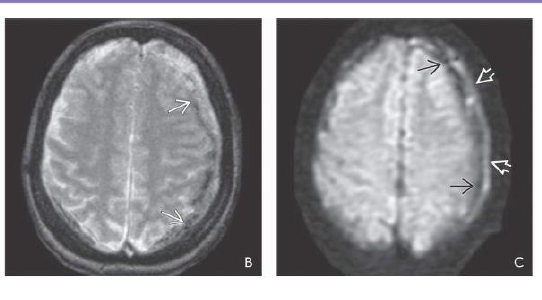

What sequence?

What is shown?

FLAIR scan in a patient 2 days after closed head trauma shows a small hypodense SDH and multiple

axonal injuries

Findings of SDH on GRE and FLAIR

T2* GRE scan shows some “blooming” in the sSDH. 2-36C. DWI shows the classic “double layer”

appearance of an sSDH with hypointense rim on the inside and mildly hyperintense rim on the outside

of the clot